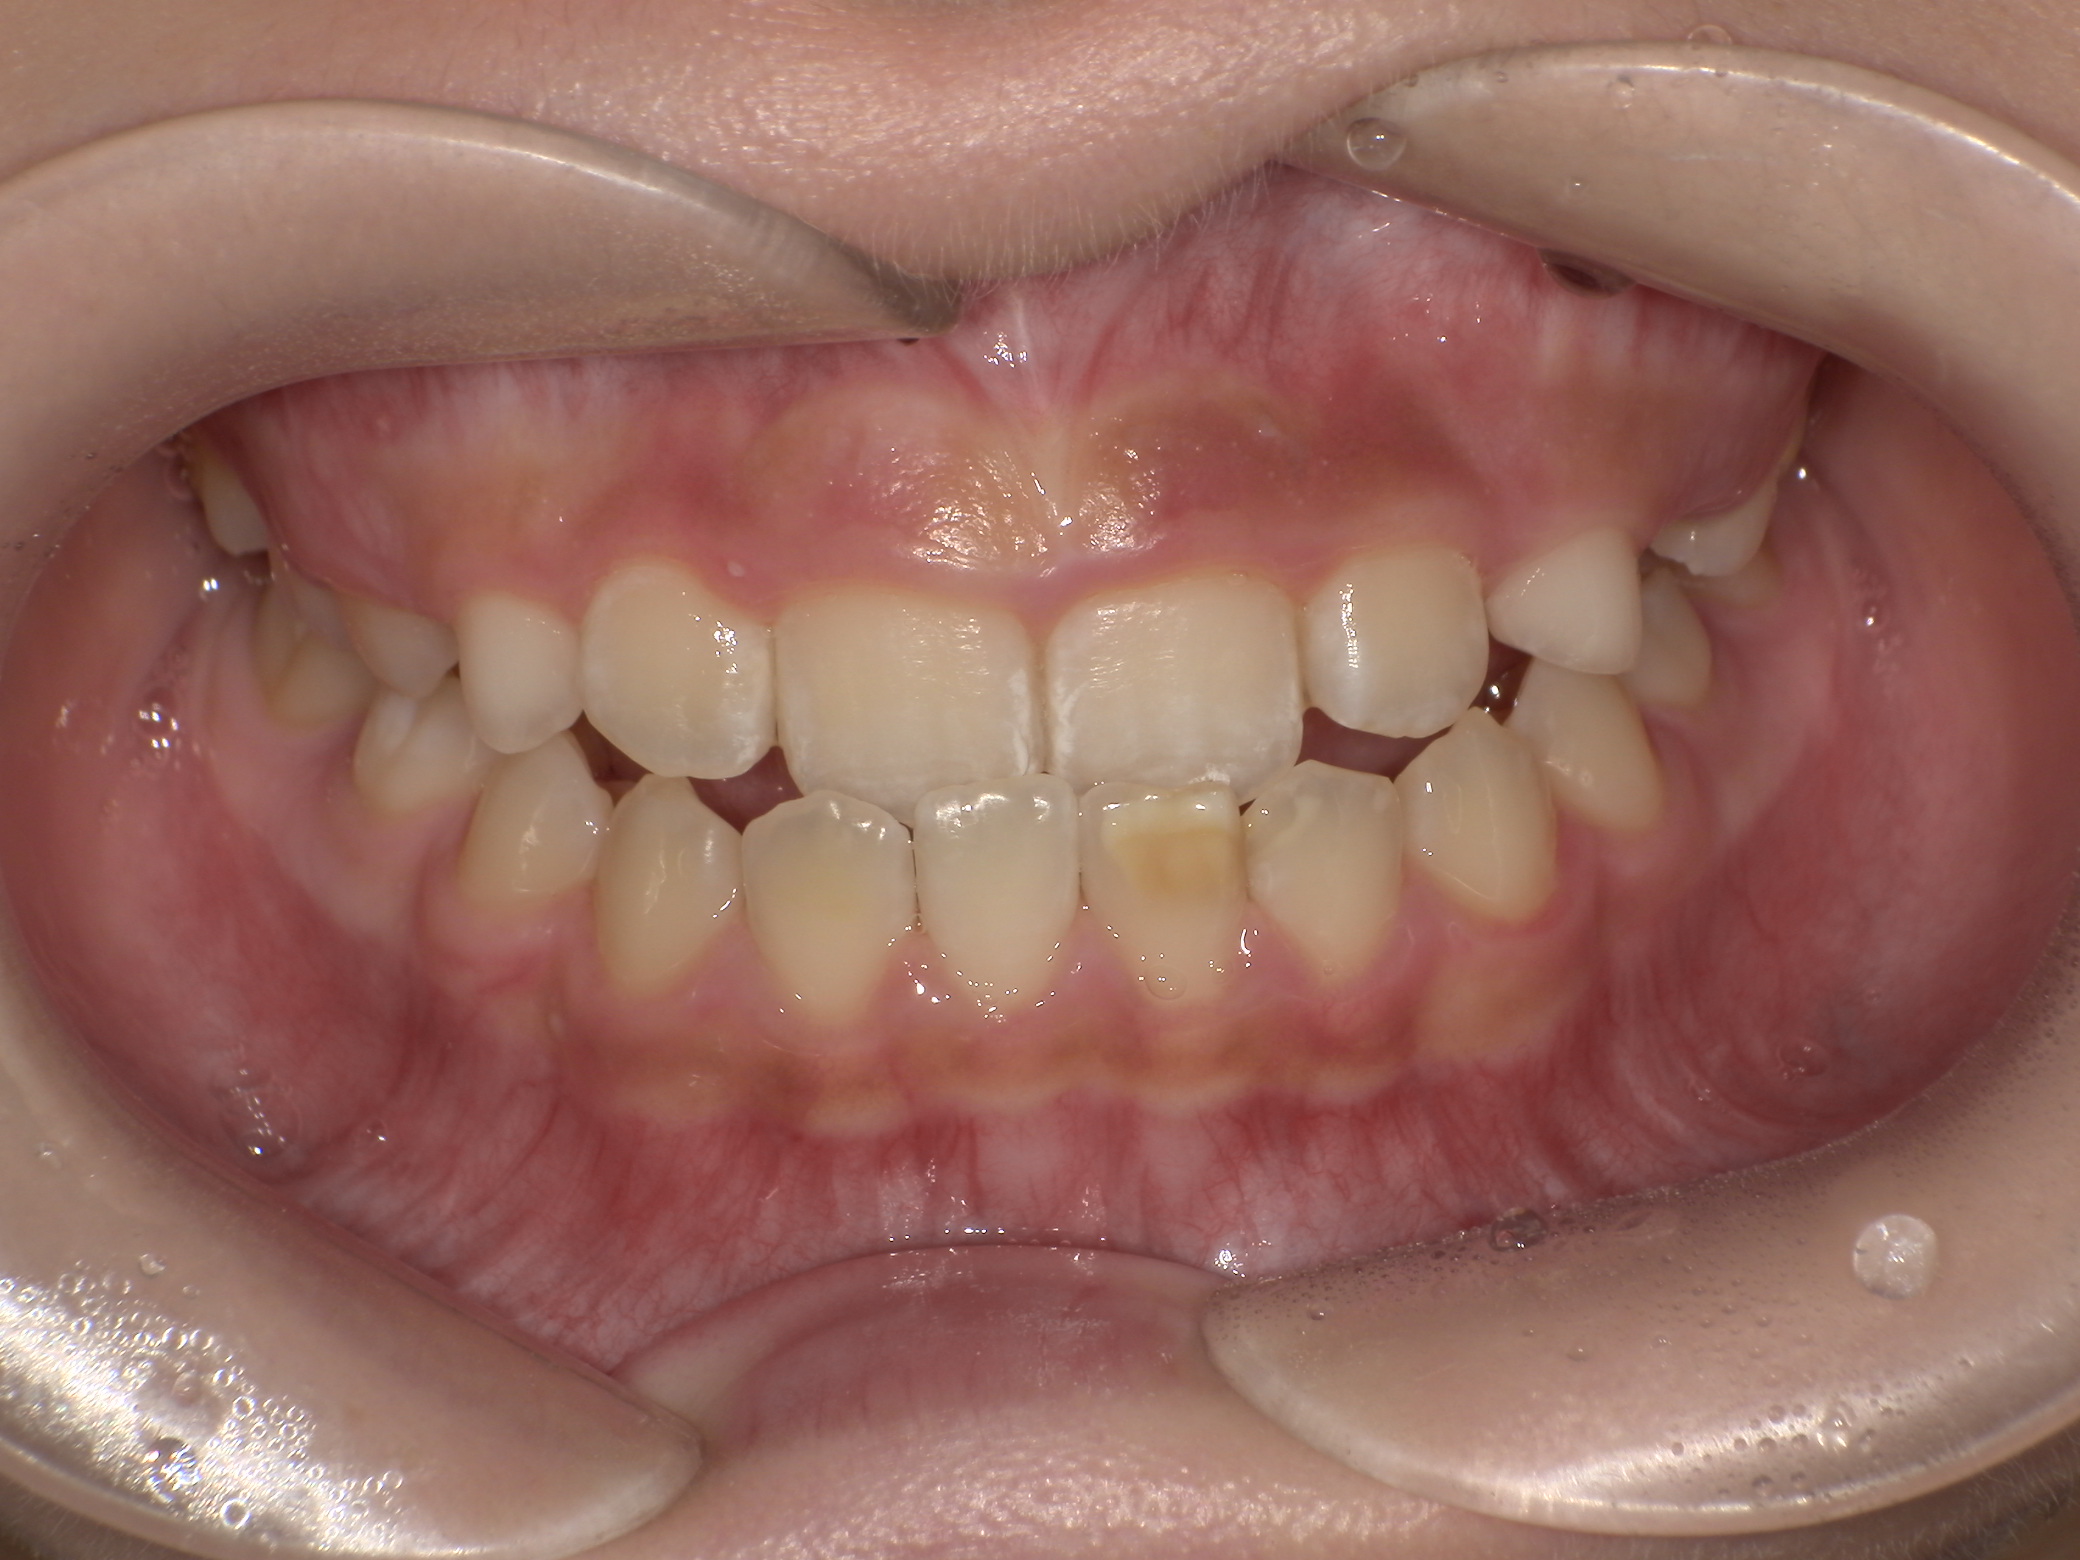

Before

治療開始前(9歳5か月)